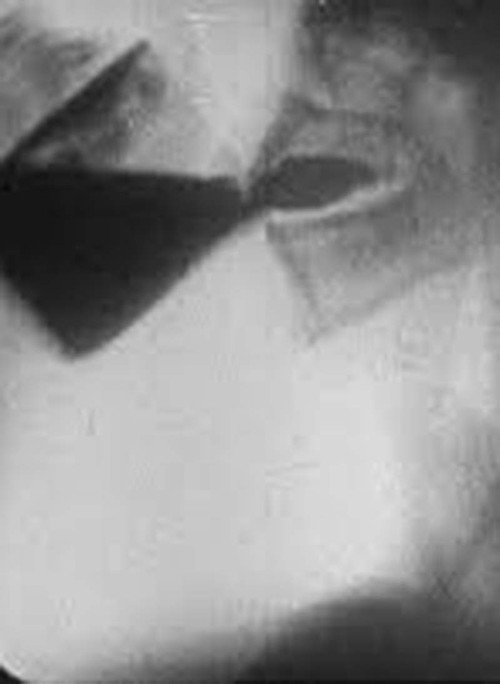

This silent b&w film has intertitles in gothic script (in German). The film features cineradiography of x-rays of eating, drinking and digestion. Solid food is consumed sideways on with a good view of the mouth, then the thorax as food and drink pass down to the stomach. Finally stools are seen forming and dropping through the intestines to the colon.